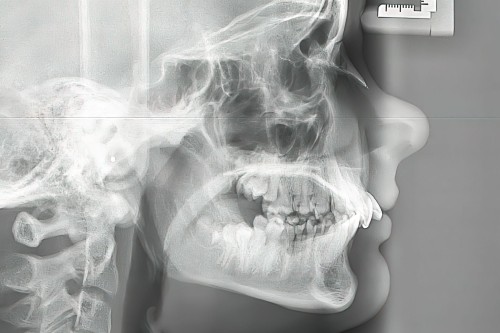

セファログラム

セファログラム(頭部X線規格写真)とは?

セファログラム(頭部X線規格写真)は、お顔の骨格を正確に捉えるためのレントゲン写真です。

決まった位置や方向から撮影することで、目視だけでは分からない骨格レベルでの情報を把握することができます。

見た目の歯並びを整えるだけでなく、お口全体の機能や将来的な安定性を考えると、その土台となる骨格の状態を知ることがとても重要になります。セファログラムでは、主に以下の情報を精密に分析します。

- 1上下のあごの大きさや位置関係

- 顎関節の状態

- 歯の傾斜や位置

- 口元のバランス